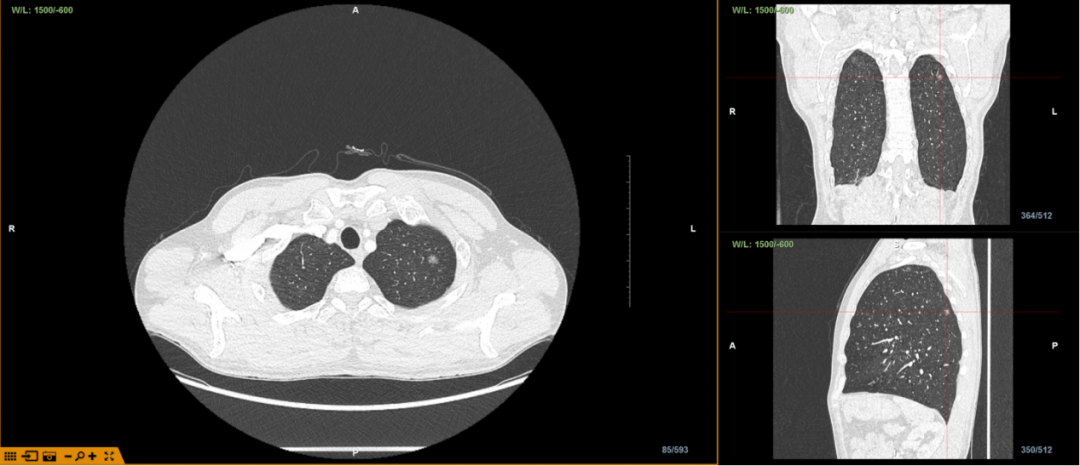

患者,男,57岁。胸部CT显示检查显示,左肺上叶结节影,恶性不除外,建议进一步检查。

经LungPro增强现实光学全肺诊疗导航系统评估分析,患者病灶位于左肺上叶尖段,大小约8*10mm,临近胸膜。为方便定位,明确诊断,呼吸与危重症医学科边翠霞主任团队与胸外科蔡海波主任团队决定应用LungPro增强现实光学全肺诊疗导航系统引导下在气道注射亚甲蓝进行病灶染色定位,然后行胸腔镜下外科手术。